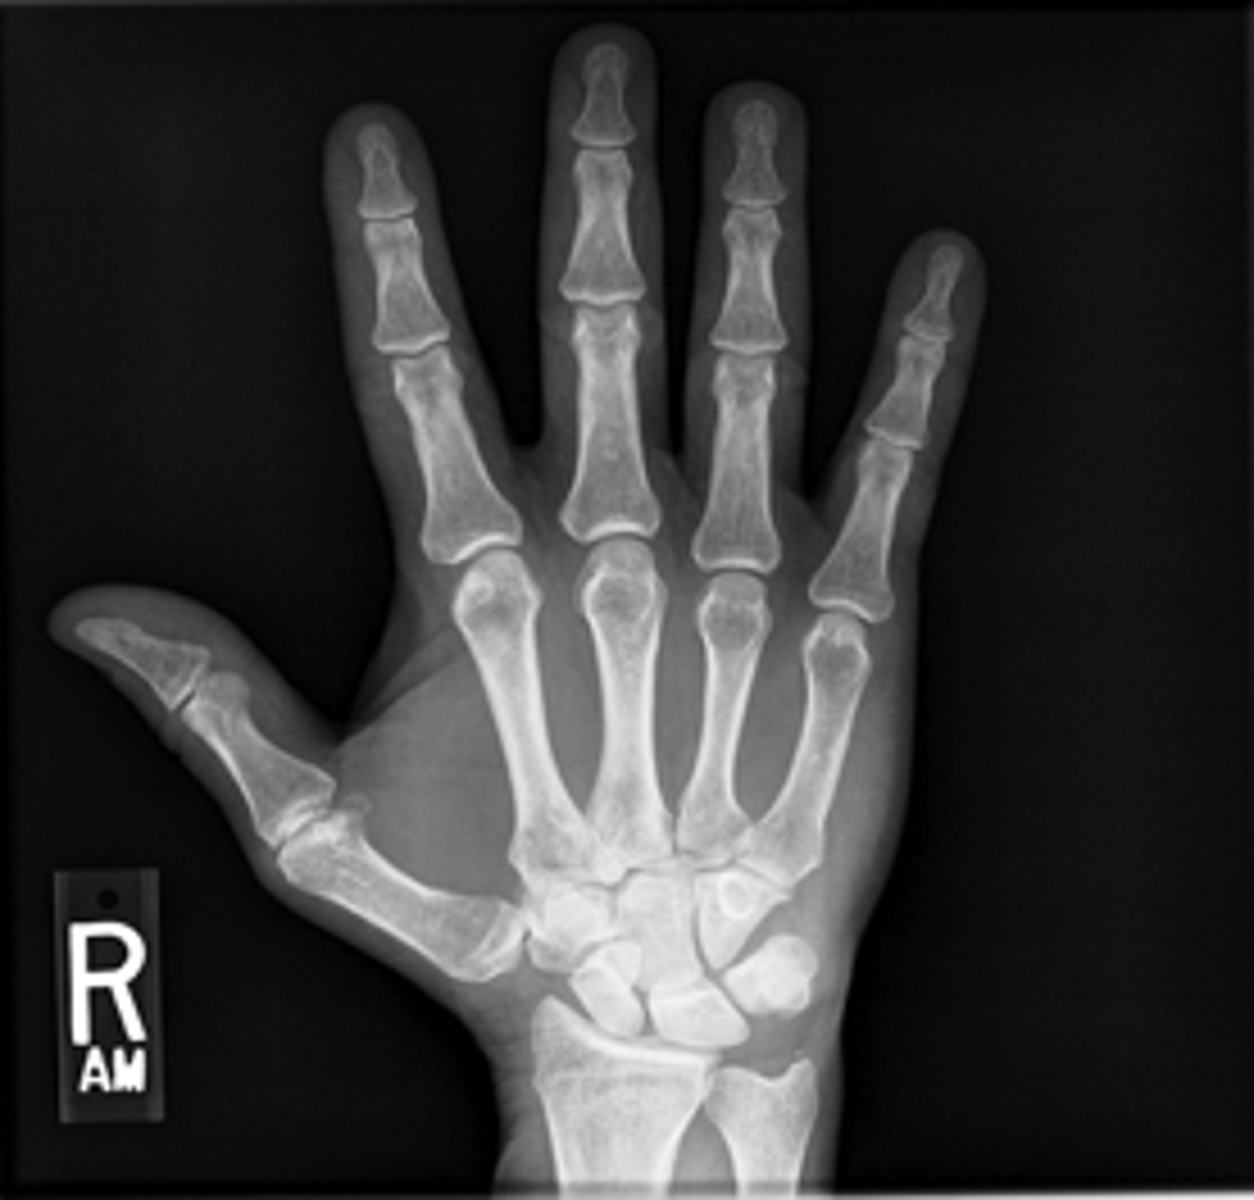

PA hand